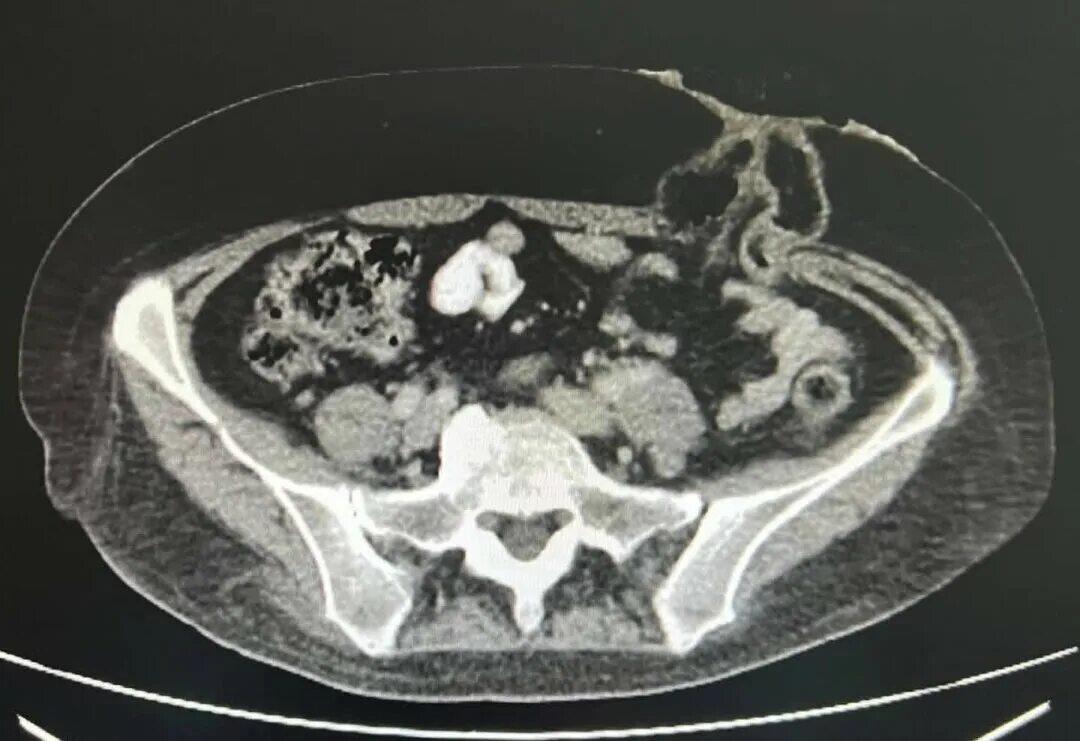

Рак прямой кт